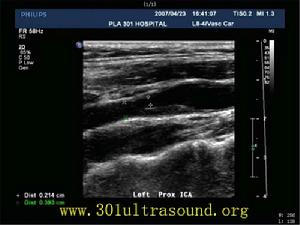

2、腰穿檢查只在不能做CT檢查、臨床又難以區別腦梗死與腦出血時進行,通常腦壓及CSF常規正常。經顱都卜勒(TCD)可發現頸動脈及頸內動脈狹窄、動脈粥樣硬化斑或血栓形成。超聲心動圖檢查可發現心臟附壁血栓、心房粘液瘤和二尖瓣脫垂。